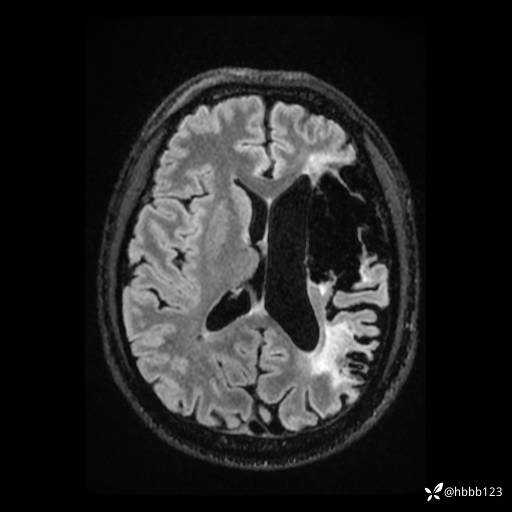

T2: